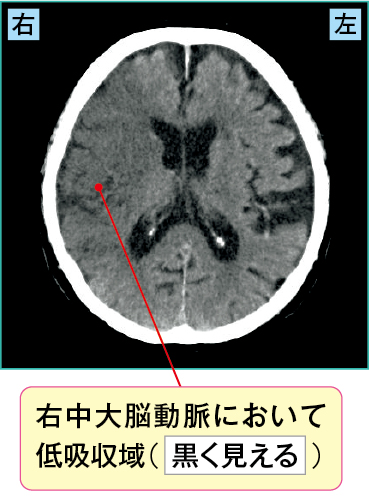

突然の意識障害が出現したため、家族が救急要請して搬送されてきた患者さんの例です。

すぐにCT(図2-1)が撮影され、右中大脳動脈領域において低吸収域を示していました。そこで脳梗塞が疑われMRIを施行し(図2-2)、その結果、DWIでは広範囲に高信号域を、ADCmapでは低信号域を認め、またT2強調像においても高信号域が認められました。

発症後、数時間が経過している急性期の右中大脳動脈領域の心原性脳梗塞と診断され、ヘパリンの投与が開始されました。

図2-1 急性期の心原性脳梗塞のCT画像

図2-2 急性期の心原性脳梗塞のMRI(DDWI、拡散強調像)